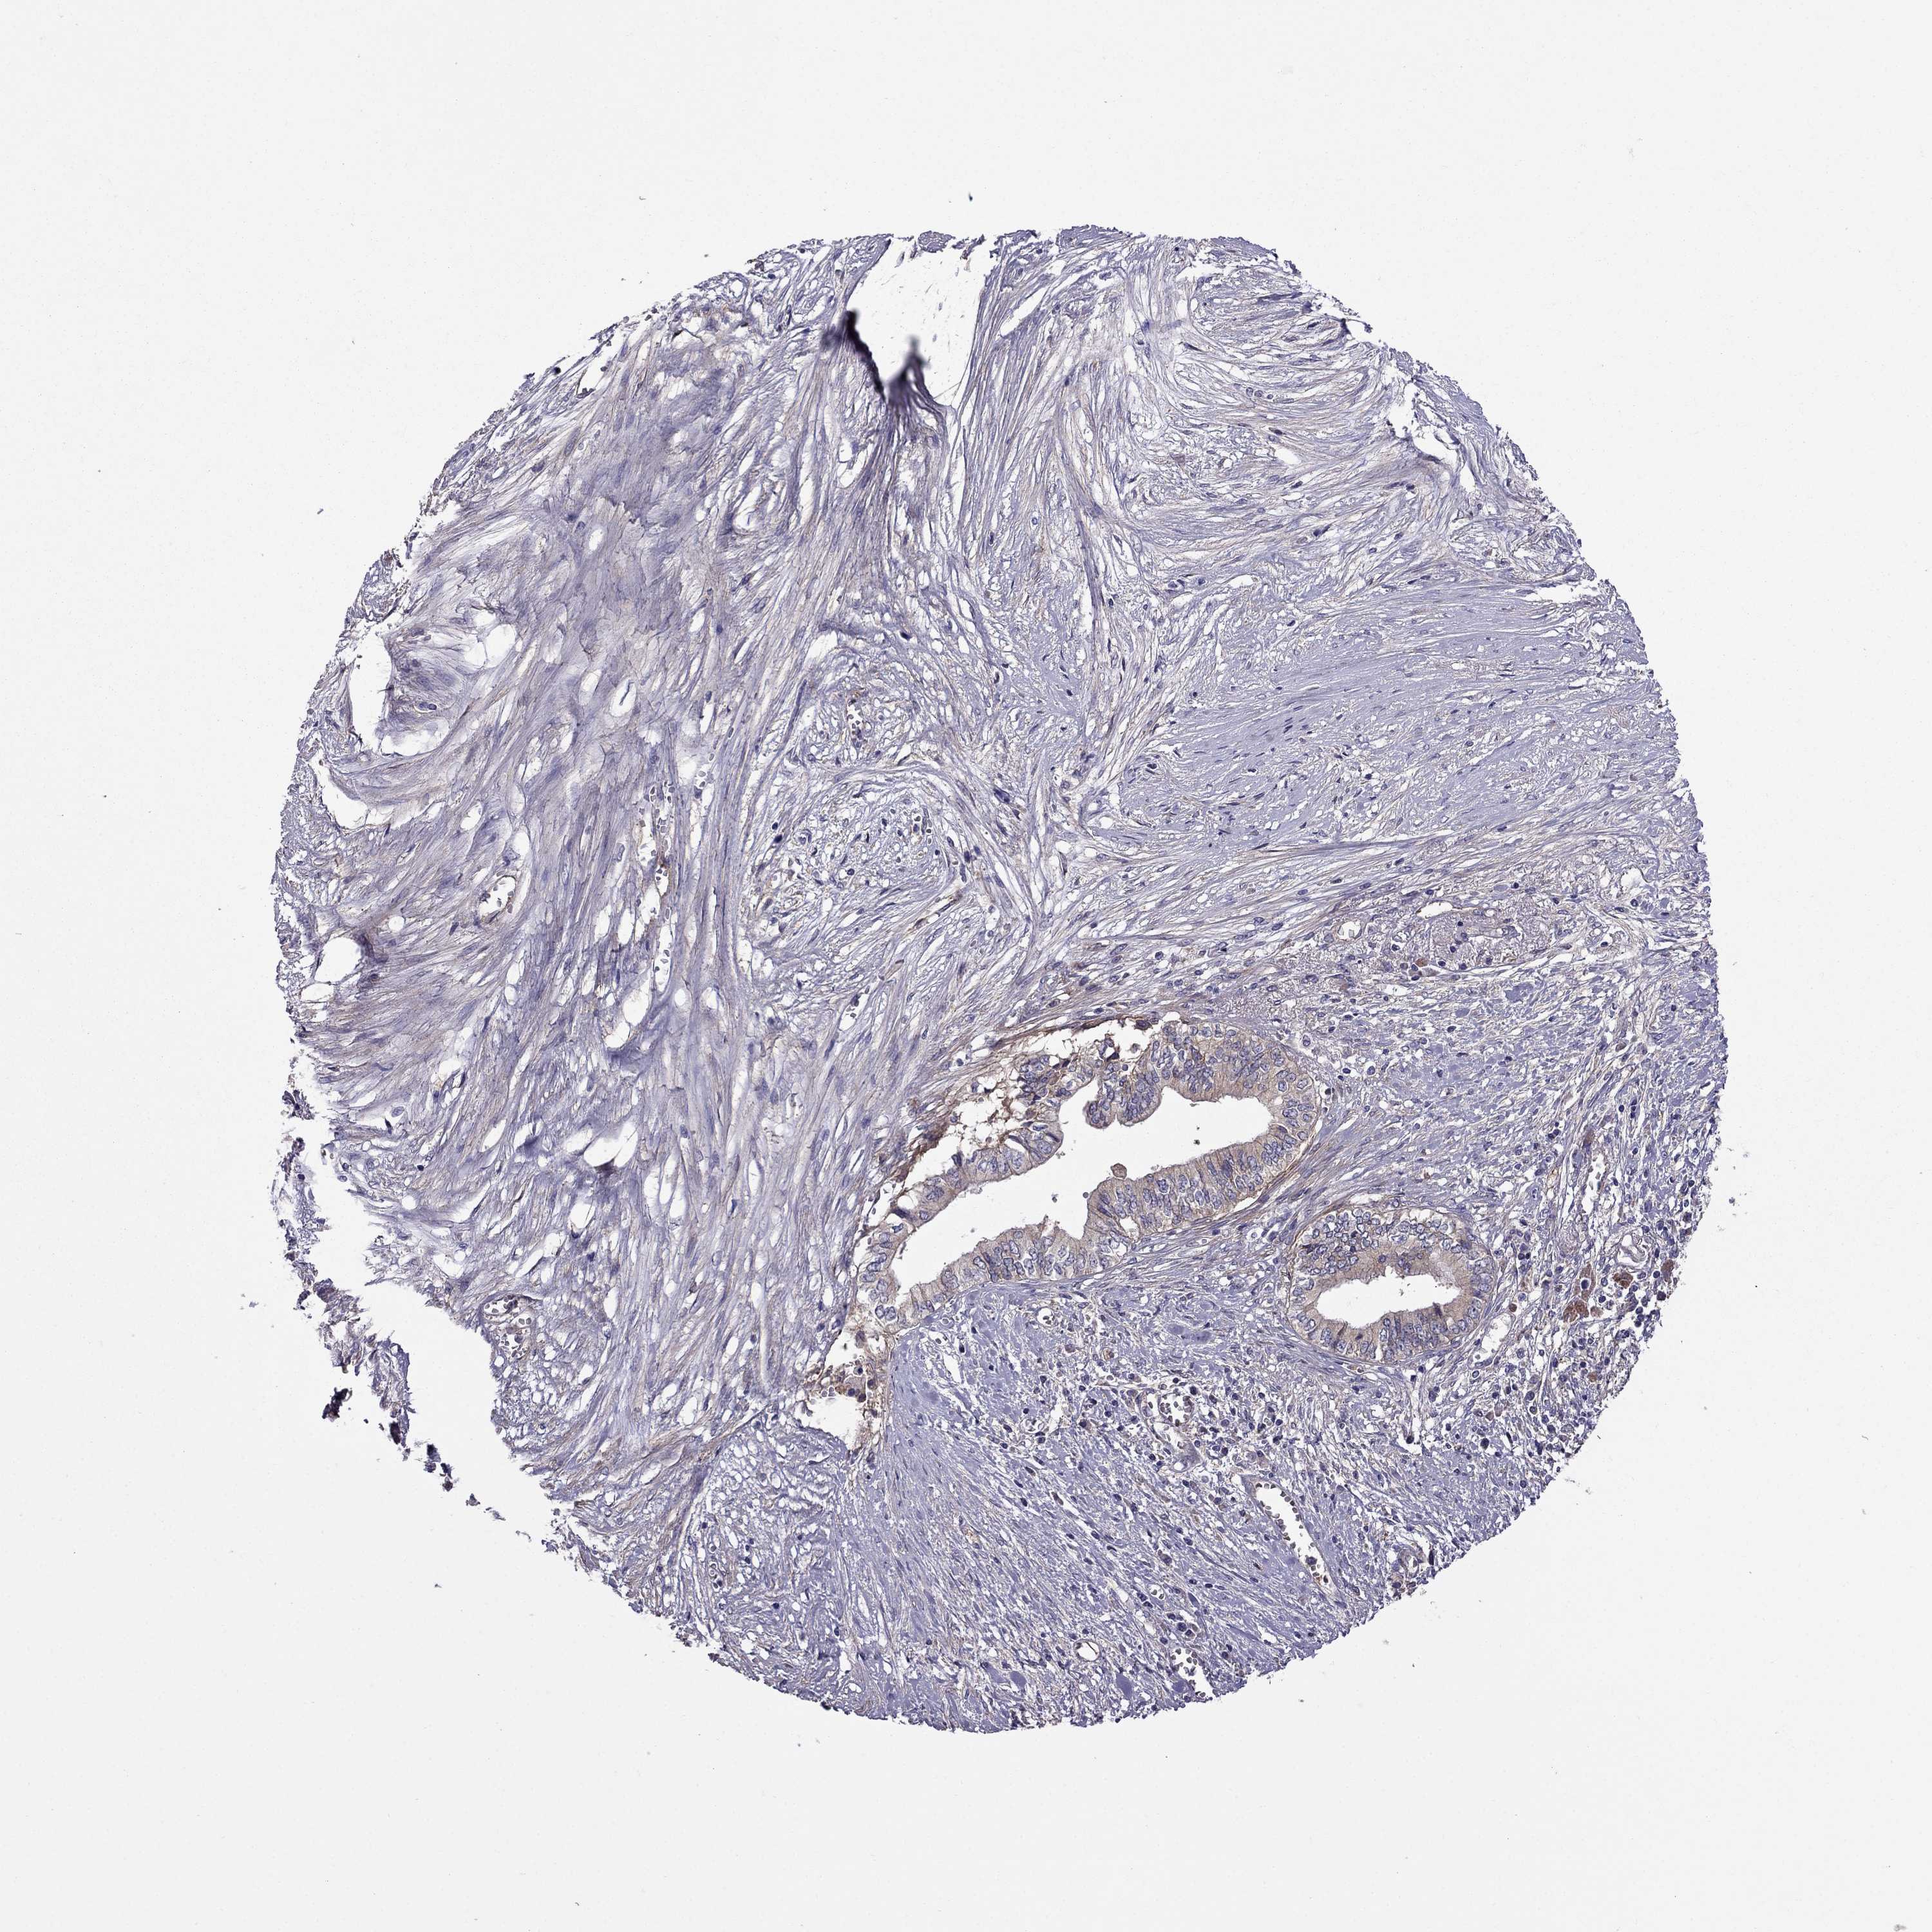

PANCREATIC CANCER - Protein expressioni

A mouse-over function shows sample information and annotation data. Click on an image to view it in a full screen mode. Samples can be filtered based on level of antibody staining by selecting one or several of the following categories: high, medium, low and not detected. The assay and annotation is described here.

Note that samples used for immunohistochemistry by the Human Protein Atlas do not correspond to samples in the TCGA dataset.

Antibody stainingi

Antibody staining in the annotated cell types in the current human tissue is reported as not detected, low, medium, or high, based on conventional immunohistochemistry profiling in selected tissues. This score is based on the combination of the staining intensity and fraction of stained cells.

Each image is clickable and will lead to virtual microscopy that enables deeper exploration of all samples and also displays staining intensity scores, fraction scores and subcellular localization as well as patient and tissue information for each sample.

Antibody HPA059297

Antibody HPA069003

Antibody CAB003434